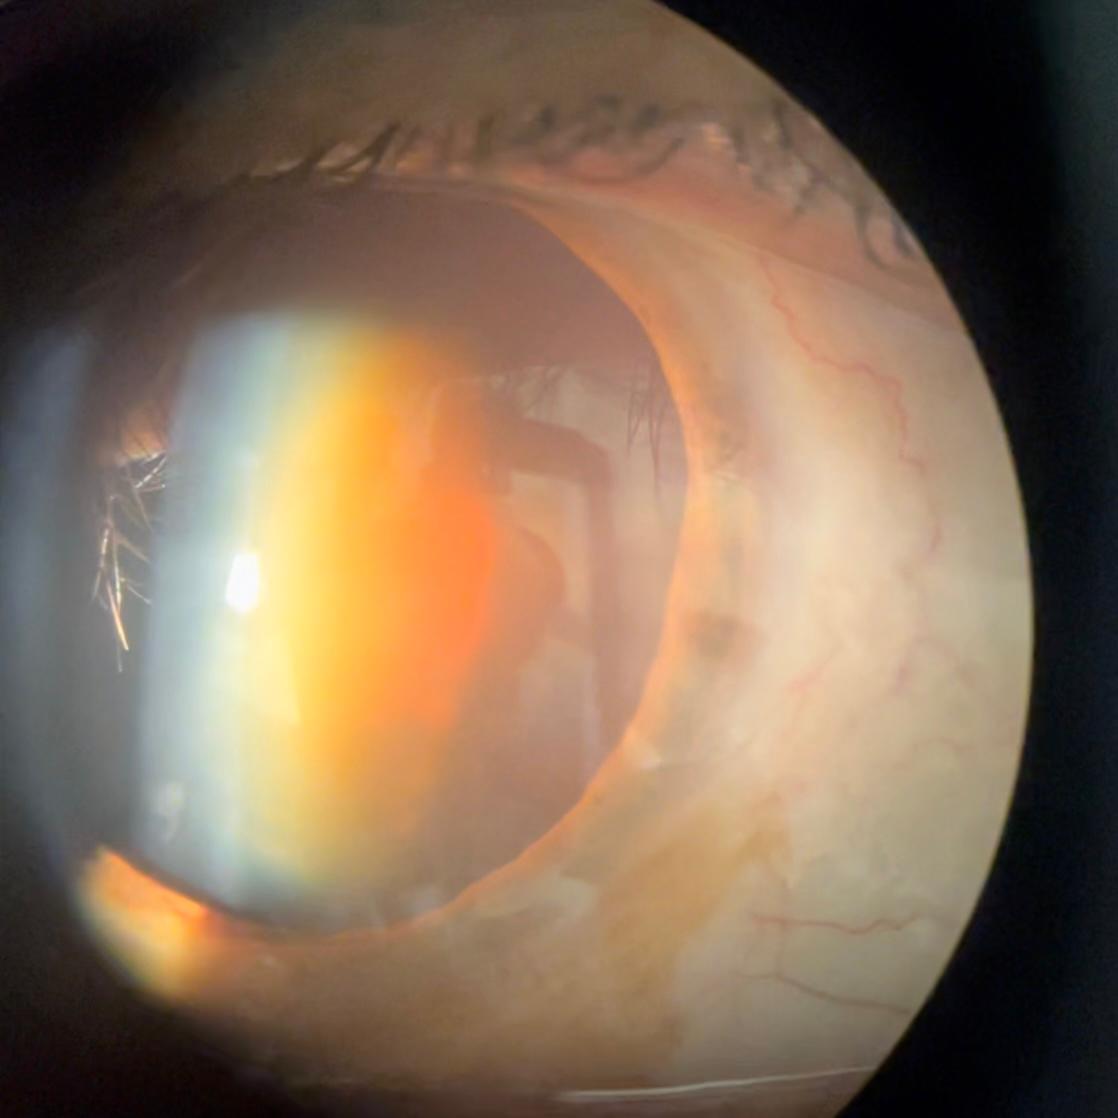

Kataraktlı Göz

Katarakt hastalığı ilerlediğinde göz merceği sertleşebilir , kalınlaşabilir, eriyebilir bir nevi çürüme durumu olabilir.

Bu durumlarda hem ameliyat zorlaşır , hem göz tansiyonu ortaya çıkabilir, hem de mercek takmak zorlaşır ve mercek takabilmek için ilave cerrahiler gerekebilir.